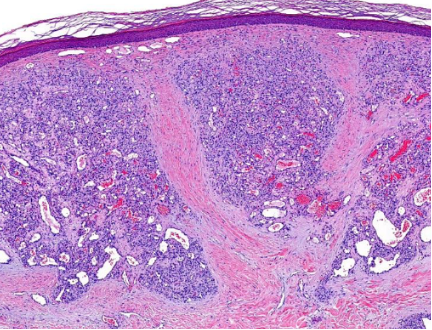

Aufgrund des raschen Größenwachstums mit möglicher Alteration des Nagelwachstums, zur sicheren Abklärung der Dignität und insbesondere auch auf Wunsch der Patientin, erfolgte die handchirurgische Entfernung der Läsion. In der Histologie bestätigte sich die Arbeitsdiagnose eines sogenannten Granuluma pyogenicums bzw. ätiologisch exakt, eines eruptiven Hämamgioms (Abb. 2).

Abb. 2. Typische Histologie eines Granuloma pyogenicum mit multiplen lobulären Kapillarkonvoluten in der Dermis mit bindegewebigen Septen und möglicher Erosion der darüberliegenden Epidermis mit neutrophiler und lymphozytärer Infiltration (a,b). Typisch ist die seitliche epitheliale Collerette (Kragenbildung).